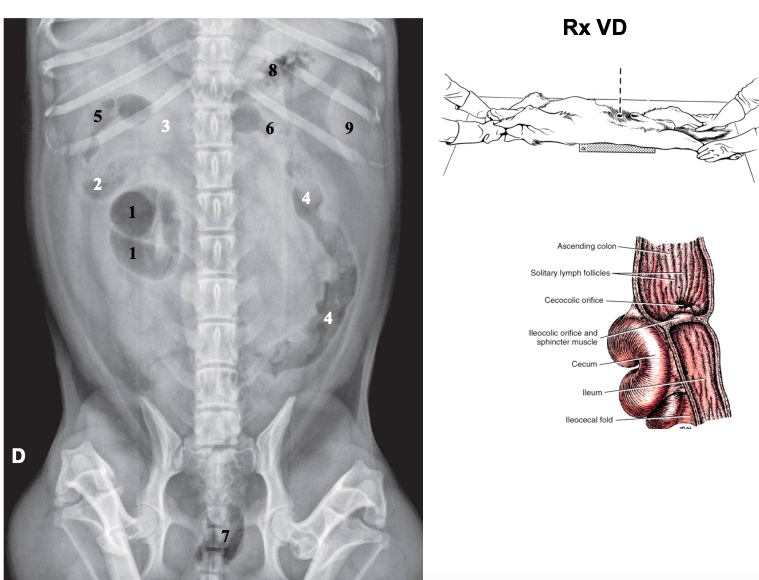

Radiografia ventrodorsal

La vertebra L2 tiene que caber entre 2,5 veces y 3,5 veces en el perro, entre 2,4 y 3 en el gato

- Bazo (fundus a la izquierda, cola a la derecha en perros, gatos se mantiene medio-izquierdo)

- intestinos (asas intestinales) Colon ascendente derecho, descendente izquierdo

En gato el bazo siempre esta en la izquierda, el perros la cola puede estar a la derecha